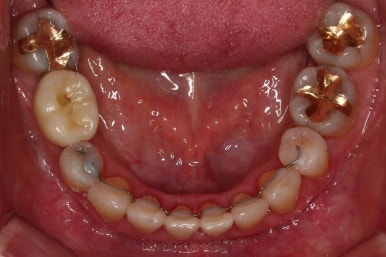

아랫니가 윗니보다 더 많이 삐뚤어 있는데요.

비밀은 바로 화살표에 있습니다.

유치 잔존

말그대로 어릴 때 빠져야 할 유치가 남아있다는 뜻인데요.

앞니 사이에 뾰족하게 남아있다 보니 자리만 많이 차지하고 있는 모습이었고 다른 영구치를 더 삐뚤게 만들었어요.

딱히 영구치가 모자라진 않는데 유치가 잔존하는 굉장히 드물고 독특한 상황이었습니다.

당연히 유치는 뽑기로 했고요.

임플란트가 이미 있을 경우

이번 환자분의 경우 임플란트가 어금니 크기보다 작게 제작이 되어 있어서 추후에 교합을 맞추기도 곤란한 상황이었어요.

그래서 교정 후에 임플란트 뿌리 부분은 그대로 사용하고 머리 부분만 재제작 하기로 했습니다.